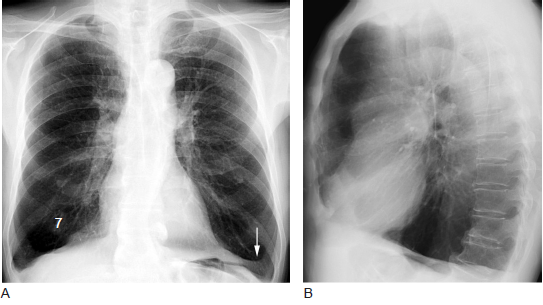

图1.1 正位及侧位胸片:膨大肺及肺气肿

如果是典型表现,还有桶状胸,胸廓前后径增加,这是常见的copd肺气肿的